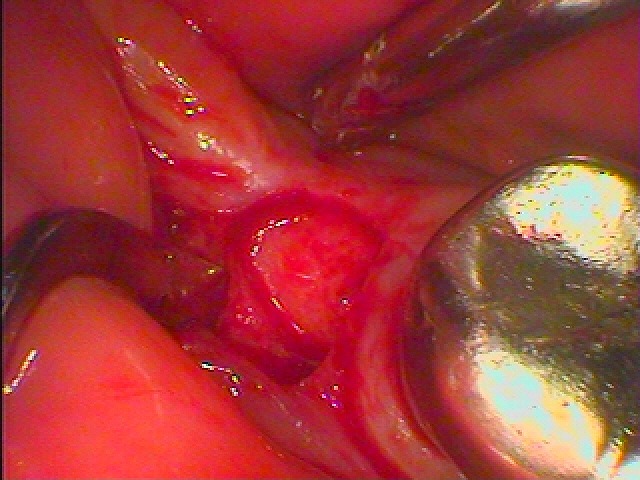

最小限で開けていきます

インプラント埋入をおこなっていきます